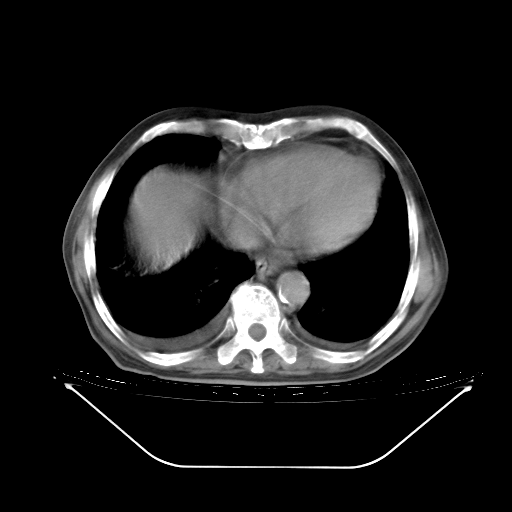

胸腹部CT,诊断意见:左上肺叶钙化灶、左侧胸膜局限性增厚并钙化、胆囊炎。描述部分肺组织呈磨玻璃样改变。